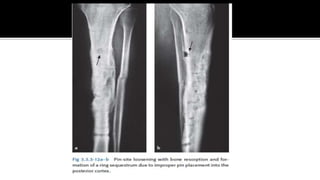

 Burning the bone  early loosening due to ring sequestrum formation

1. Pin-track care

 On x-ray a seam of bone resorption can be observed and mechanically the pin